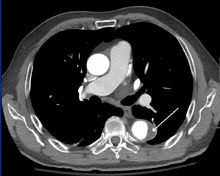

Computed tomography

Computed tomography angiography is a fast, noninvasive test that gives an accurate three-dimensional view of the aorta. These images are produced by taking rapid, thin-cut slices of the chest and abdomen, and combining them in the computer to create cross-sectional slices. To delineate the aorta to the accuracy necessary to make the proper diagnosis, an iodinated contrast material is injected into a peripheral vein. Contrast is injected and the scan performed using a bolus tracking method. This type of scan is timed to an injection to capture the contrast as it enters the aorta. The scan then follows the contrast as it flows through the vessel. It has a sensitivity of 96 to 100% and a specificity of 96 to 100%. Disadvantages include the need for iodinated contrast material and the inability to diagnose the site of the intimal tear.